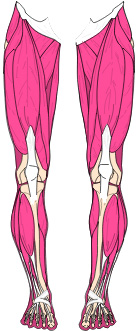

Die Muskeln benötigen die Knochen-Hebel als Kraft-Übersetzung.

Befindet sich Spannung und Gegenspannung nicht im Gleichgewicht, verzieht es das Skelett. Dadurch verändern sich Knochen- und Gelenkstellungen, was zu einseitiger Überbelastung führt und vielmals als Arthrose betrachtet wird.

Diese Fehl-Spannungslinien verursachen Überdehnungsschmerzen, Durchblutungs- und Lymphsystem-Störungen. Die Spannungslinien führen auch zu inneren Blockaden von Organen, Organ-Verbindungen, die wiederum unterschiedliche Beschwerden verursachen können.

Im Wissen, das sich kein Skelett aus eigenem Antrieb bewegen kann. Für den Zusammenhalt der Knochen, Gelenke, Wirbelkörper und die Bewegung sind die Muskeln, Sehnen und Bänder verantwortlich.

Muskulatur / Sehnen und Bänder

Muskulatur, Sehnen und Bänder sind für die Bewegung und den Zusammenhalt des Skeletts verantwortlich. Die Muskeln benötigen die Knochen als Kraftübersetzung. (ein gesunder Mensch ca. 656 Muskeln)